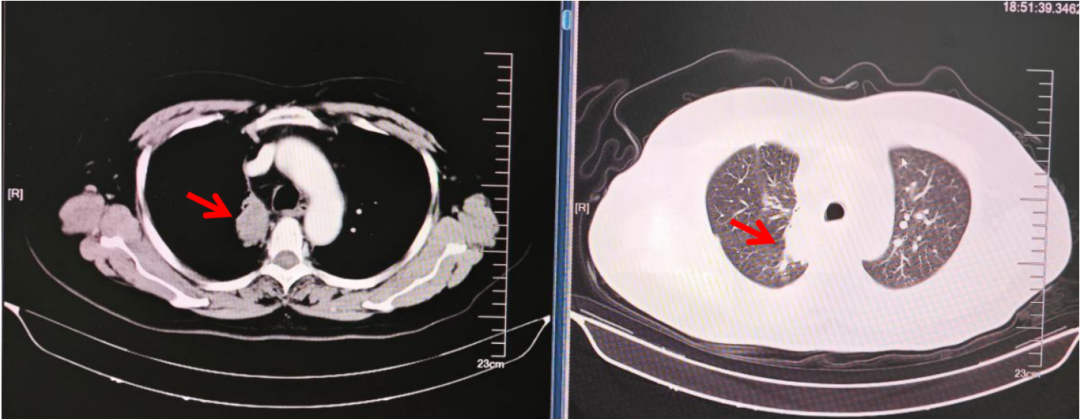

影像学检查:2025.02.05:胸腹部增强CT:右肺门-右肺上叶不规则软组织影,整体较前范围增大,积气较前减少;远端肺组织阻塞性肺炎、肺不张,较前范围稍增大。纵隔及右肺门多发淋巴结,部分较前增大。双肺散在小结节,部分较前增大。双肺少许炎性改变,较前相仿;双侧胸膜增厚,局部较前明显。甲状腺密度欠均,较前相仿。双肾低密度灶,右肾大者较前增大,转移?余较前相仿。T9及L5椎体骨质破坏,转移可能,较前相仿。(如下图所示)